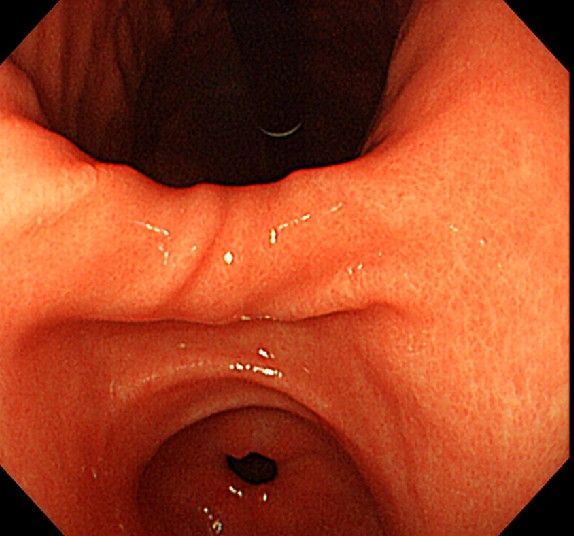

위 내시경을 찍었는데 위염 종류 사진을 알 수 있을까요? (사진 많습니다..)

한달 전 쯤에 소화불량과 속쓰림이 3개월 동안 약을 먹어도 낫지 않아 위 내시경을 찍었는데 위에 염증이 많이 있다는 이야기를 들었습니다...그런데 상태가 얼마나 안 좋은지 어떤 종류의 위염인지에 대해서는 물어봐도 안 알려주셔서 여기에라도 올려서 여쭈어봅니다... 제 상태가 얼마나 심각한 걸까요..

사진상으로 보아서는 정상에 가까운 점막상태이거나 약간의 표재성 위염이 있는 정도로 보입니다.

홍반성 위염이 있으며 경증의 역류성 식도염이 있습니다